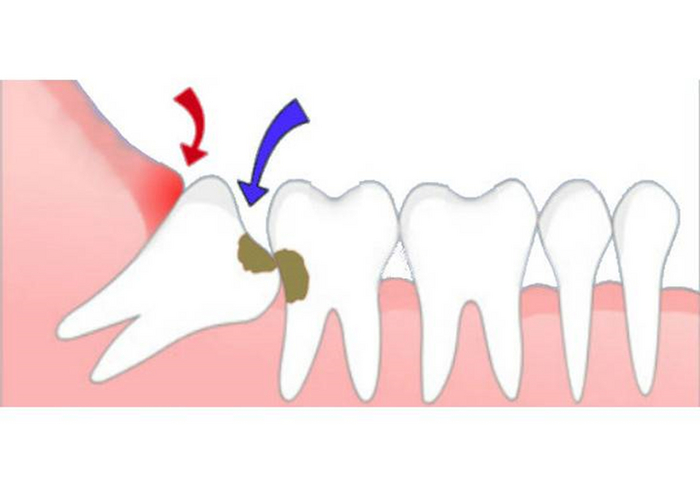

Прорезавшиеся, дистопированные, полуретинированные и ретинированные.

Дистопированные зубы- прорезались, но не там, где надо и так, как надо

Полуретинированные- вылезли из кости, а через слизистую не шмогли

Ретинированные- те, которые сидят полностью в кости

Несмотря на отличия в расположении, принцип их удаления примерно одинаков

После того, как мы сделали анестезию, мы по необходимости производим разрез и отслаиваем слизистую оболочку с надкостницей от кости (слизисто-надкостничный лоскут) и бормашиной с водяным охлаждением выпиливаем костную стенку. Почему по необходимости? Потому что эти этапы зависят от степени прорезанности и расположения зуба. Чем более прорезан зуб, тем меньше разрез и меньше убираем кости. Иногда обходимся одним разрезом, иногда даже разрез не приходится делать, а просто распиливаем зуб. Короче, смотрим по ситуации.